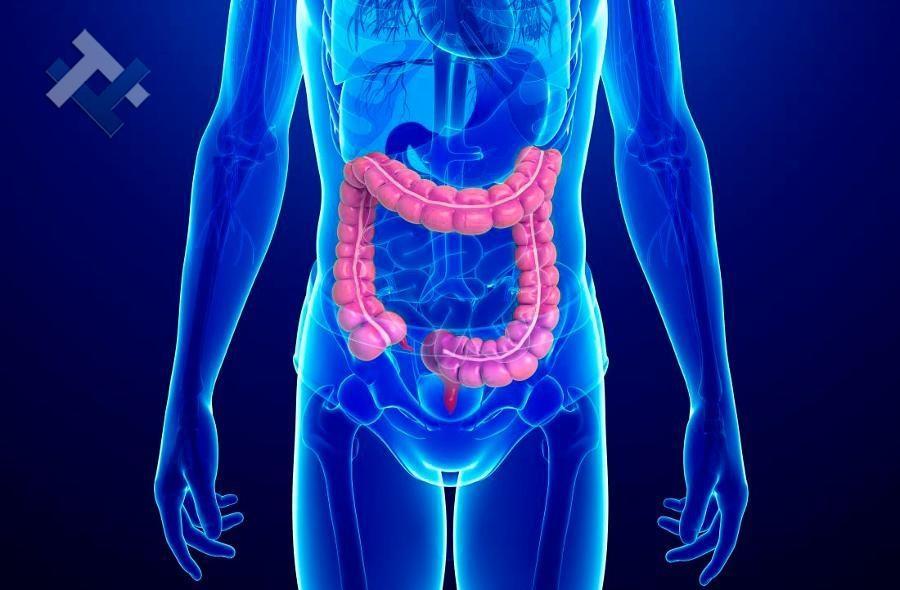

Ο Γενικός Χειρουργός Λιάγκος Γεώργιος MD PhD εκτελεί τις επεμβάσεις Λαπαροσκοπικά, Ενδοσκοπικά, Ανοιχτά Ελάχιστα Επεμβατικά και με Laser. Η θεραπεία εξατομικεύεται σε κάθε ασθενή ανάλογα με τις ανάγκες του. Αναλαμβάνει περιπτώσεις όπως κήλες και κοιλιοκήλες (αντιμετώπιση βουβωνοκήλης, αντιμετώπιση ομφαλοκήλης, θεραπεία επιγαστρικής κήλης, κήλη των αθλητών (Σύνδρομο κοιλιακών προσαγωγών), αντιμετώπιση μετεγχειρητικής κήλης, θεραπεία Μηροκήλης), πέτρες στη χοληδόχο κύστη, λαπαροσκοπική χολοκυστεκτομή, αντιμετώπιση Κύστη Κόκκυγος με λέιζερ (laser), παθήσεις πρωκτού, χειρουργική laser σύγχρονων κυκλικών ινών (αιμορροΐδες αντιμετώπιση, θεραπεία αιμορροϊδων με laser (LHP), αφαίρεση αιμορροΐδων με υπερήχους (HALL-RAR), χωρίς Χειρουργείο με ελαστικούς δακτυλίους (Τεχνική BARON-RBL), θεραπεία ραγάδας πρωκτού (Ραγάδα δακτυλίου), θεραπεία περιεδρικού συριγγίου, θεραπεία περιεδρικού αποστήματος, κονδυλώματα πρωκτού Θεραπεία, δερματικό ράκος (Skin tag) εκτομή, αντιμετώπιση Kνησμού, καρκίνος πρωκτού θεραπεία), παθήσεις Δέρματος, χειρουργική με laser CO2, αφαίρεση μορφωμάτων δέρματος - βιοψίες, αφαίρεση ελιάς (Σπίλου), σμηγματογόνος κύστης θεραπεία, αφαίρεση λιπώματος, είσφρυση όνυχος χειρουργείο, καρκίνος δέρματος θεραπεία, οξεία σκωληκοειδίτιδα, παθήσεις Λεπτού και Παχέος Εντέρου, ειλεός λεπτού εντέρου, εκκολπωμάτωση (Εκκολπωματίτιδα) σιγμοειδούς, καρκίνος παχέος εντέου, κολοστομίες, port χημειοθεραπείας κ.α. εξυπηρετώντας Παγκράτι και γύρω περιοχές.